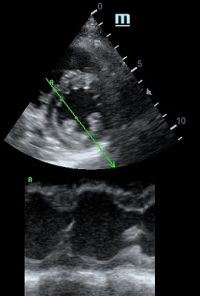

Но как же провести стандартные измерения в М-режиме, если мы его не использовали? На помощь приходит функция Free Xros M – анатомический М-режим. Имея записанную в память прибора видео петлю, мы можем провести линию М-режима в любом месте, при этом корректируя изначально не оптимальный угол.

Возможности применения функции многогранны: от измерения толщины стенок левого желудочка, движения створок митрального клапана и кооптации нижней полой вены до оценки сократимости миокарда как глобально, так и по сегментам.

Какие показатели можно использовать при анатомическом М-режиме помимо привычных срезов через конец створок митрального клапана или синуса Вальсальве?

TAPSE - показатель амплитуды движения латеральной части кольца трикуспидального клапана, позволяет количественно и быстро оценить систолическую функцию правого желудочка, норма которого составляет более 17 мм. Главным условием является проведение линии М-режима параллельно стенке правого желудочка в апикальном четырех камерном сечении, что легко достигается при Free Xros.